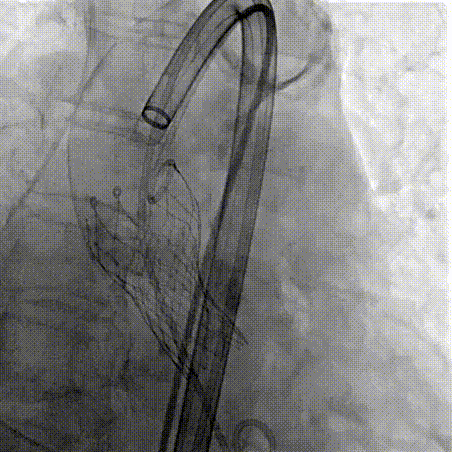

Step 4.输送系统进入:过弓性能优异,悬空通过,整体过程未将鞘管顶起至弓顶部

过弓示意图

Step 10.验证器械同轴性,完全同轴